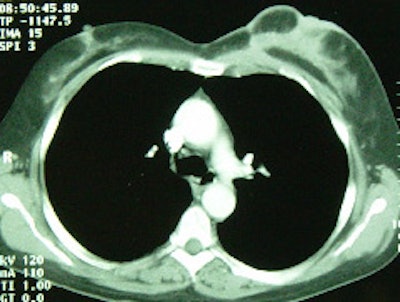

FDG PET exam for the evaluation of locoregional recurrence: The patient shown in the case below had a history of breast cancer and had developed left chest pain. She presented for the evaluation of possible metastatic disease. The CT scan revealed extensive soft tissue thickening in the left breast which was felt possibly related to scar from prior surgery and radiation therapy. There was a 2 cm lymph node in the left axilla (not shown) which was concerning for metastatic disease. Axial (center) and coronal (right) images from the patients FDG PET exam demonstrated marked increased FDG accumulation within the left breast corresponding to the soft tissue abnormality on CT. There were also multiple foci of increased uptake within the the left axilla. Biopsy revealed recurrent breast cancer. Case courtesy of CTI, The power behind PET. |

|